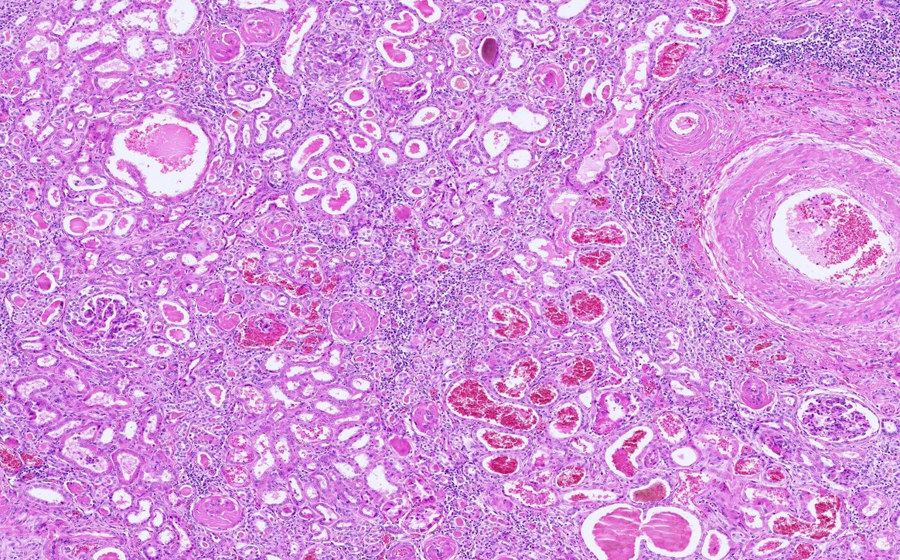

Slide 3: Glomerulonephritis - chronic

Histologic section of kidney from a patient with chronic glomerulonephritis. (click here to review normal tissue)

Image 3 - 50X

Slide 3 - Image 3